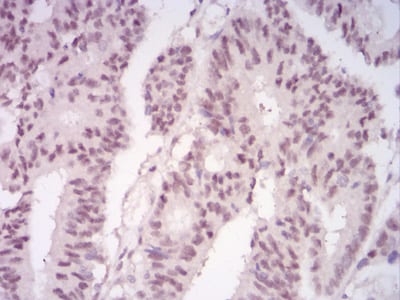

分类: 科研抗体货号: 30883别名: TRKB; trk-B; GP145-TrkB应用: IHC反应种属: Human